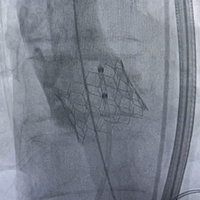

手术经股动脉入路,使用21#预扩球囊进行跨瓣预扩,后送入球囊扩张式介入瓣输送系统,成功植入一枚25# Renatus介入主动脉瓣,手术全程顺利,患者血流动力学稳定。最终介入主动脉瓣植入位置理想,功能表现出色,DSA及经食道超声观察无瓣周及瓣中反流。主动脉瓣峰值流速由术前3.7m/s降至1.95m/s,平均压差由术前32mmHg降至5.7mmHg。

瓣膜释放 术后主动脉根部造影